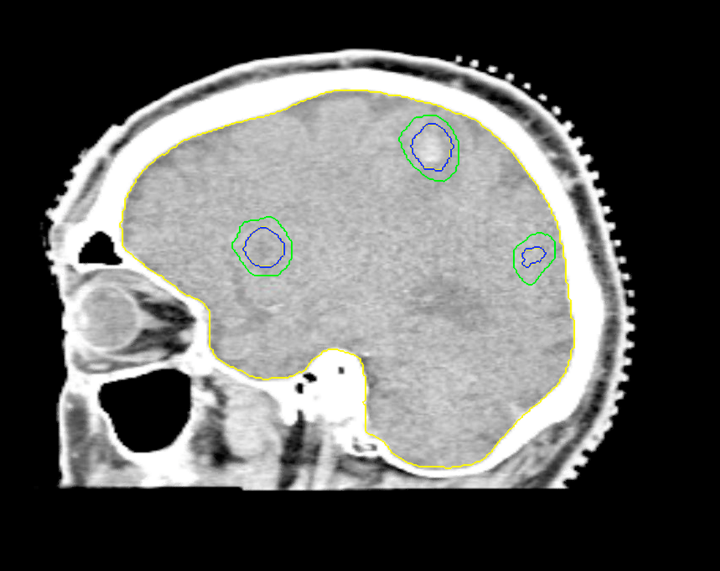

Planning CT Images